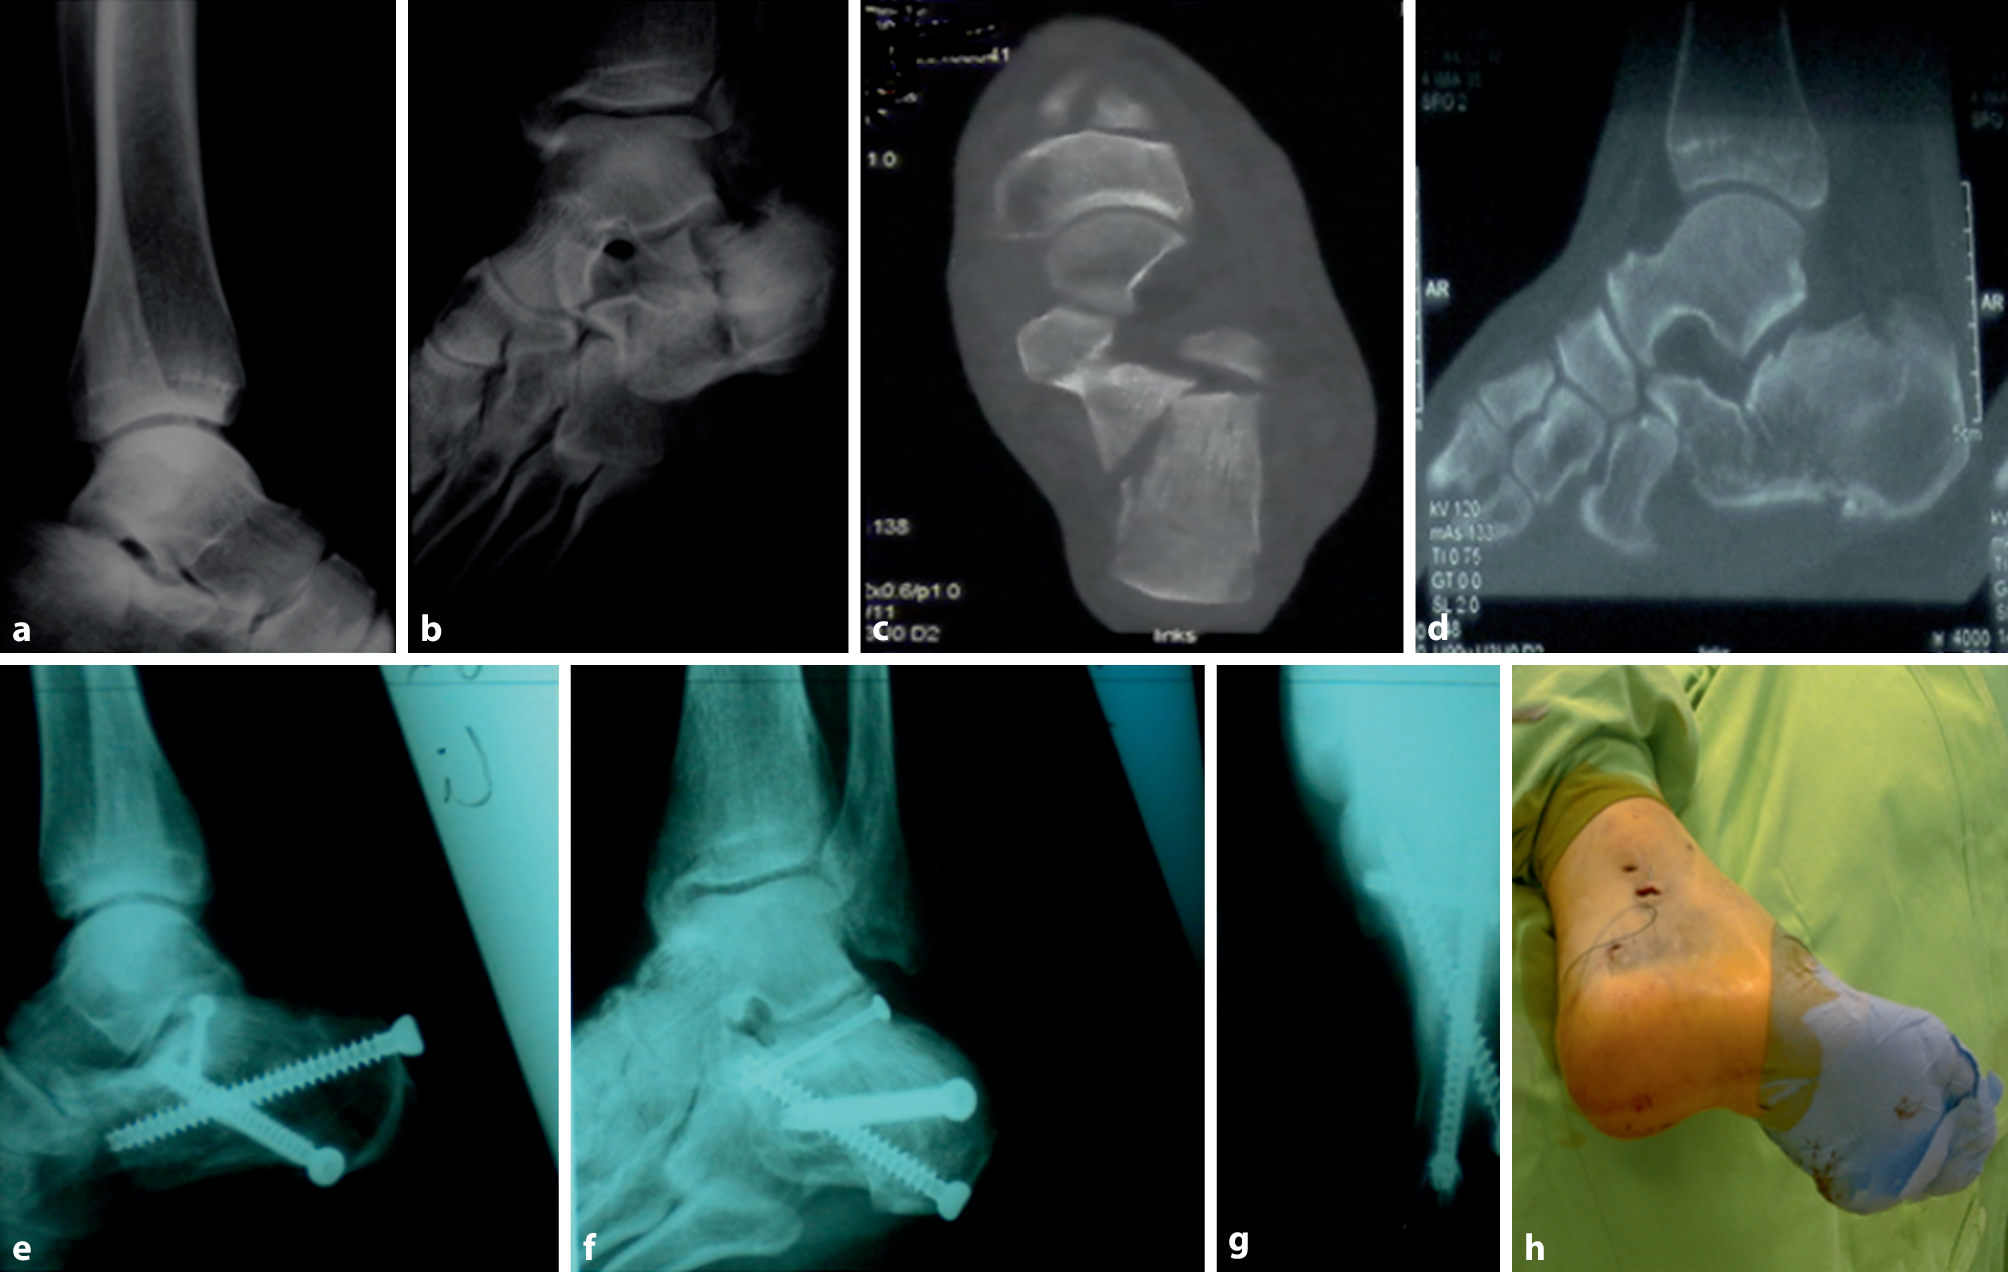

Finally, the distractor was removed and the stab incisions closed with simple sutures. An elastic bandage is applied postoperatively and the injured foot is kept non-weight bearing for 8 weeks. Toe and ankle range of motion exercises can be started immediately after the swelling has subsided. A patient case is displayed in Fig. 3.

Fig. 3

Patient case. Patient with intra-articular calcaneal fracture after fall from a great height. Sanders IIA type fracture, treated with 2‑point distractor fixation technique. a Preoperative lateral X‑ray and b preoperative axial X‑ray. Computed tomography (CT) image cd). e Postoperative lateral X‑ray shows good reconstruction of Böhler’s angle and Gissane’s angle. f Postoperative oblique X‑ray shows good reduction of calcaneal height. g Postoperative axial X‑ray shows good reduction of calcaneal length. h Intraoperative incision picture